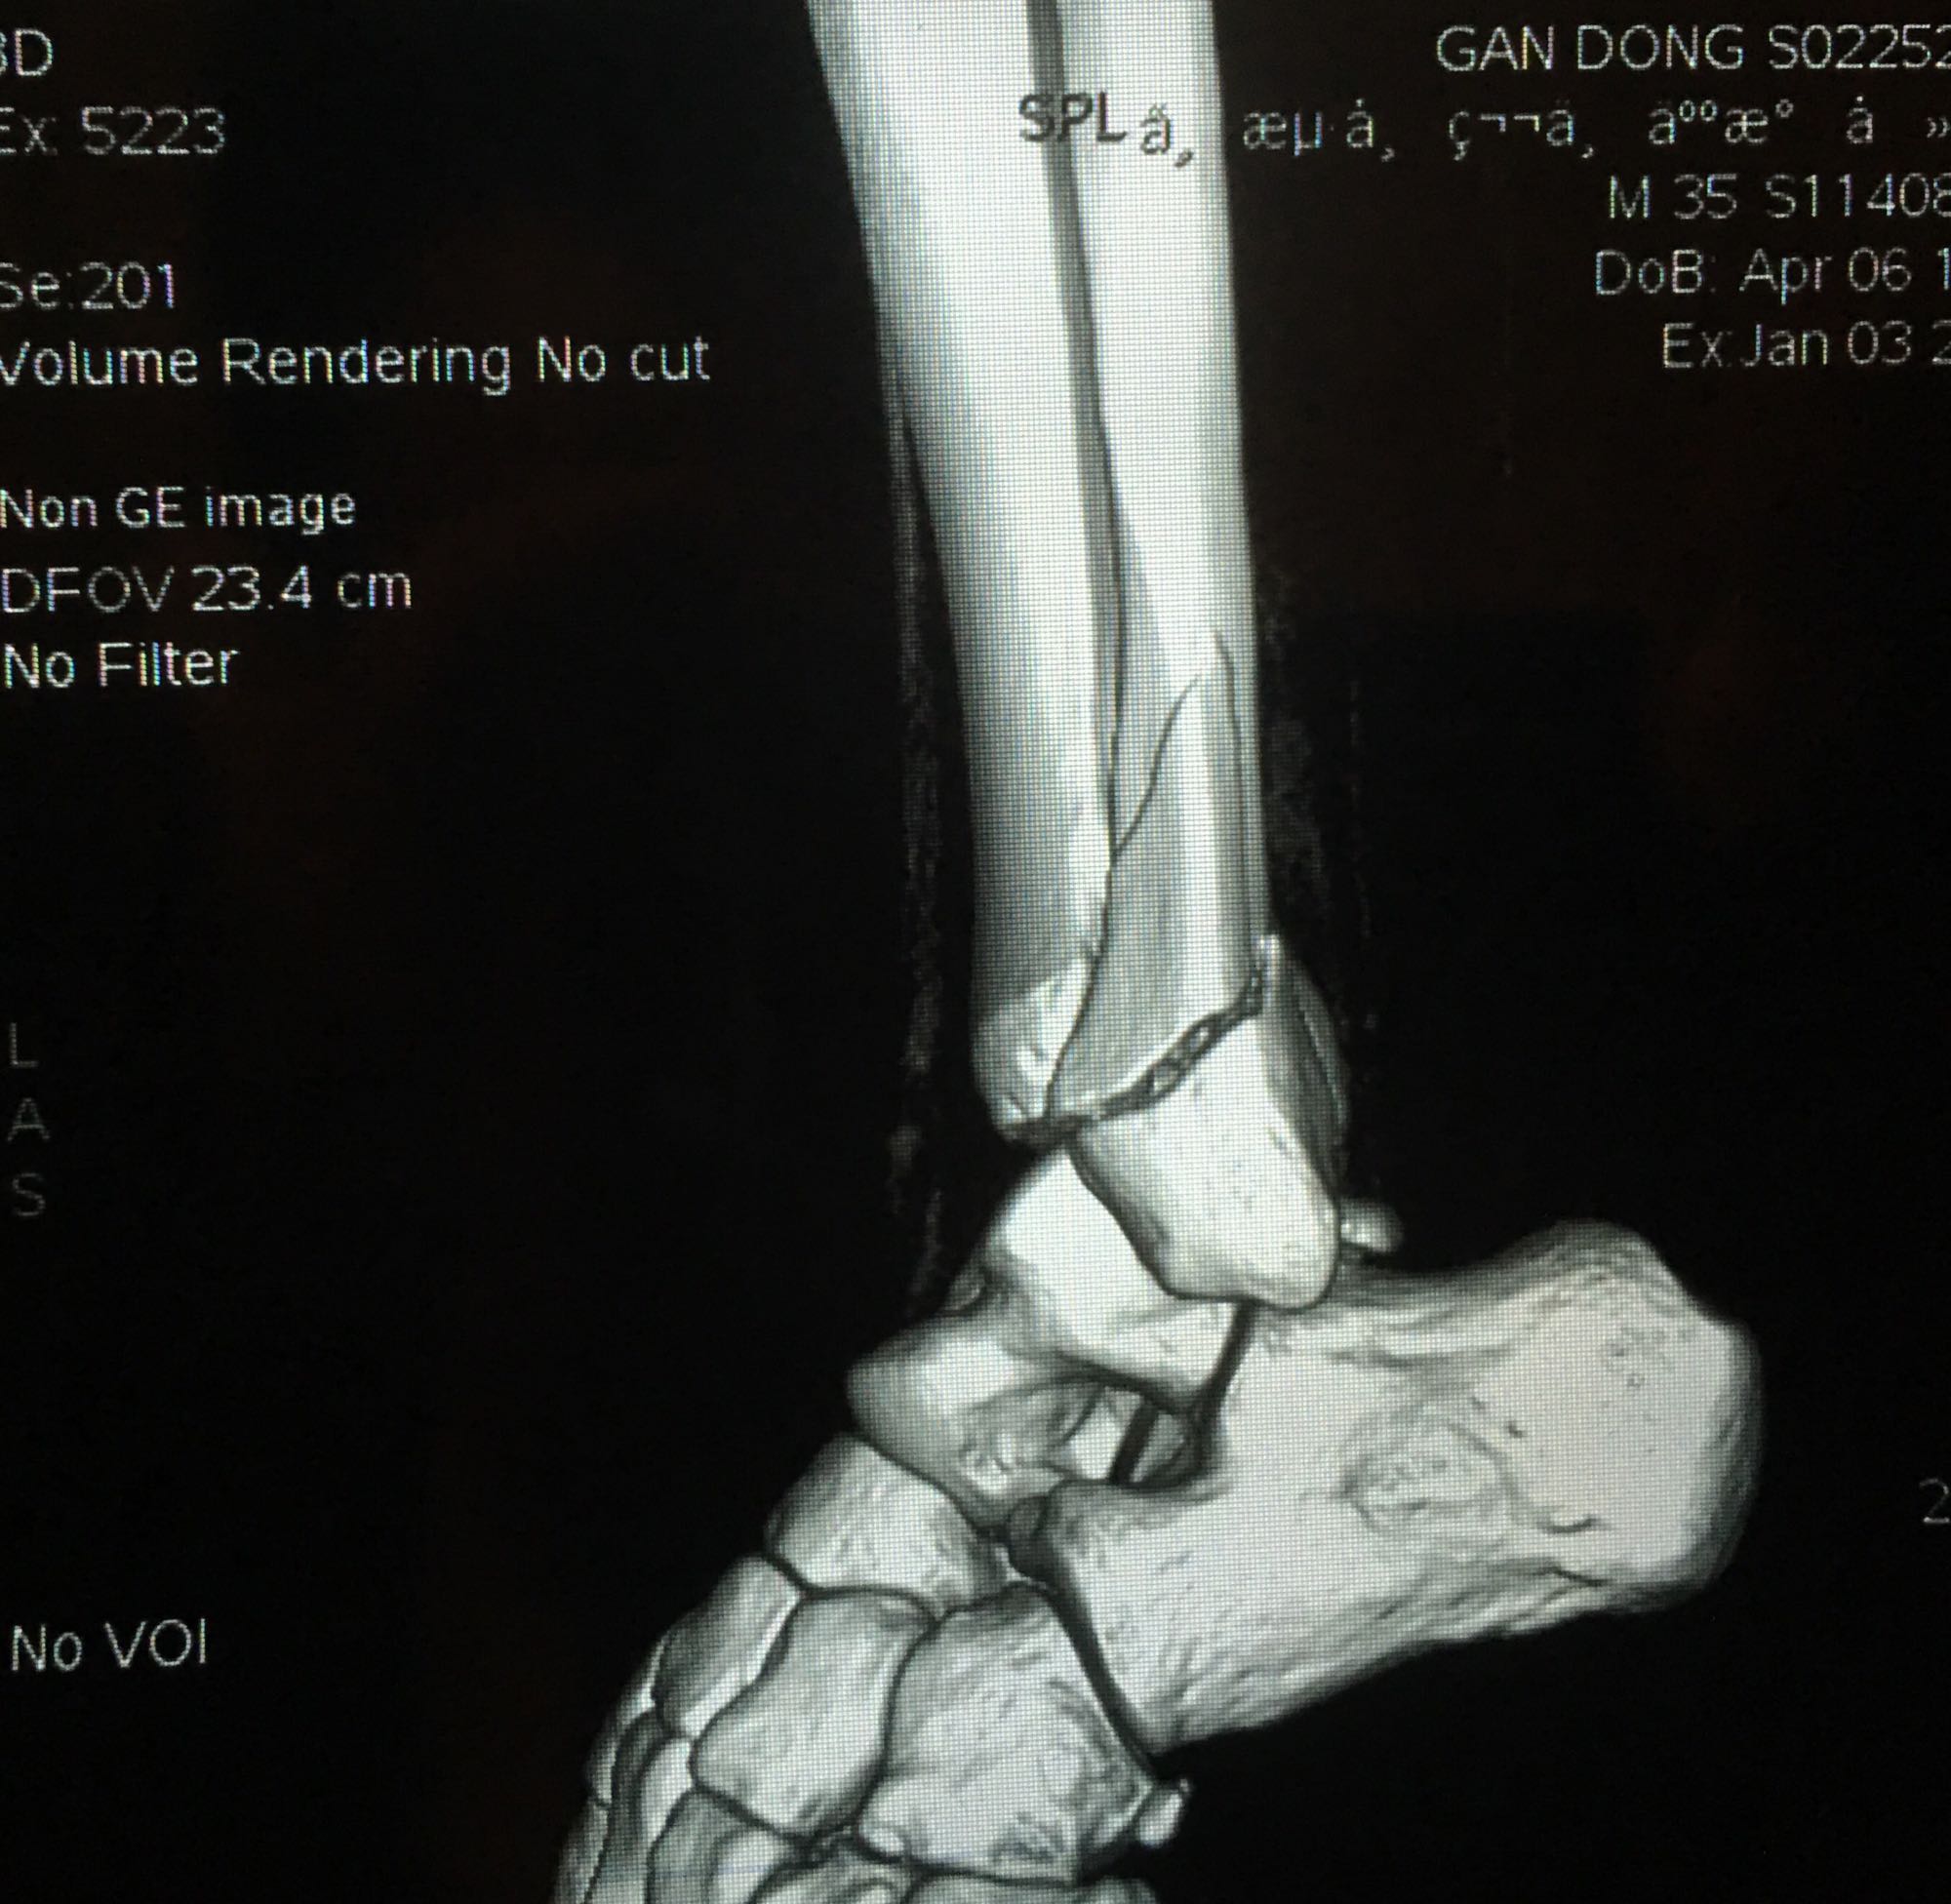

腓骨靠近踝关节处骨折,已经第七天了,西医建议手术,中医说不手

三踝骨折吧

腓骨靠近踝关节处骨折,已经第七天了,西医建议手术,中医说不手术固定好也可,迷茫中……

这个不是近关节骨折,这个是关节内骨折,关节腔肯定伤到了。手术并正确康复训练的话后遗症小,保守治疗后期康复很痛苦,同时高风险有后遗症